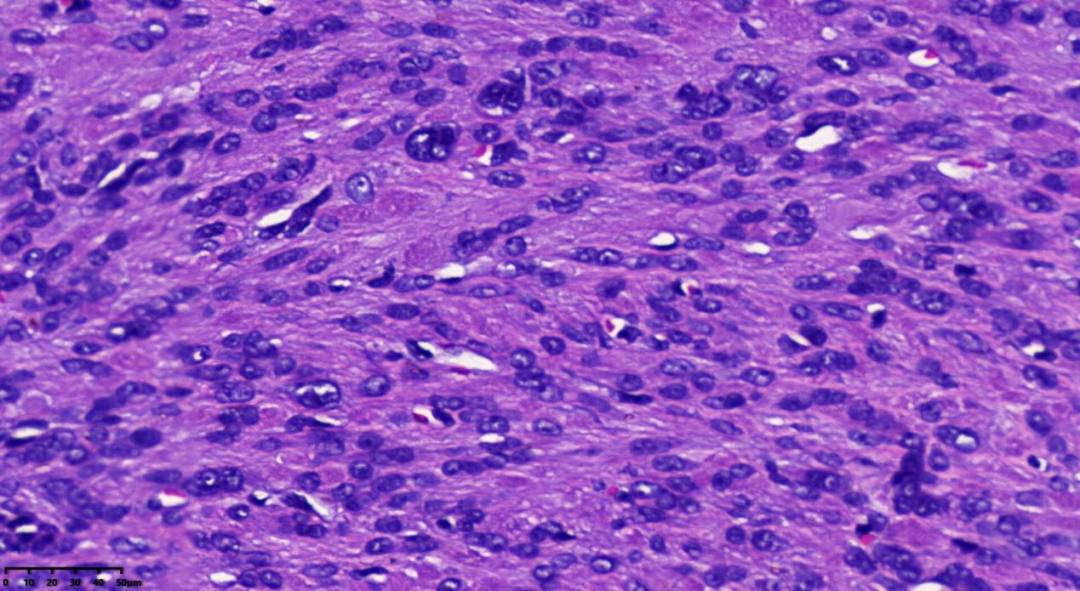

肿瘤细胞密度相对较高,肿瘤间质出现鹿角样血管

肺泡样水肿结构

细胞异型,见多核细胞;嗜酸性核仁,可见胞质内嗜酸性小体

细胞丰富,链状排列的卵圆形核,核异型,见嗜酸性核仁

链状排列的卵圆形核,可见奇异性核;嗜酸性核仁,可见核仁周围空晕

可见胞质内嗜酸性小体

肿瘤细胞密度相对较高;间质内常出现鹿角样血管;由于间质常伴有水肿,故形成肺泡样水肿结构;散在分布奇异型细胞及多核细胞;细胞核呈卵圆形;细胞核有时出现链状排列;可见胞质内嗜酸性小体;细胞核中可见突出的嗜酸性核仁,且核仁周围可见空晕。

常为轻度的核不典型性,核分裂象<5/10HPF。